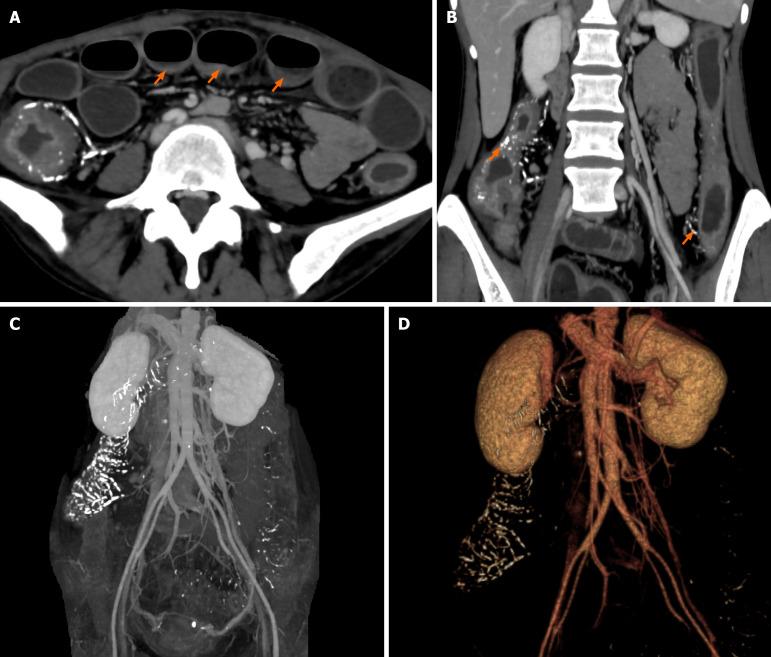

We report the case of a 44-year-old woman with chief complaints of abdominal pain, vomiting and decreased defecation. One year prior, the patient was asymptomatic and therefore misdiagnosed with inflammatory bowel disease based on incidental findings on an abdominal computed tomography (CT) scan. The present abdominal CT scan revealed an intestinal obstruction, diffuse thickening of the entire colon wall and calcification of the mesenteric and colonic veins. Colonoscopy revealed multiple ulcerations and extensive dark purple discolouration of the oedematous mucosa. Colonic transit studies suggested a decrease in colonic motility. IMP was considered the underlying cause of her pseudoileus, which was potentially linked to her consumption of Chinese medicinal teas for more than 30 years. The patient underwent conservative medical treatment, and her symptoms gradually improved. She exhibited no signs of ileus or other significant discomfort at the outpatient follow-up one year after the discontinuation of Chinese herbal tea consumption.

IMP can present with symptoms of pseudoileus as initial complication. Clinicians can use CT and colonoscopy for differential diagnoses.